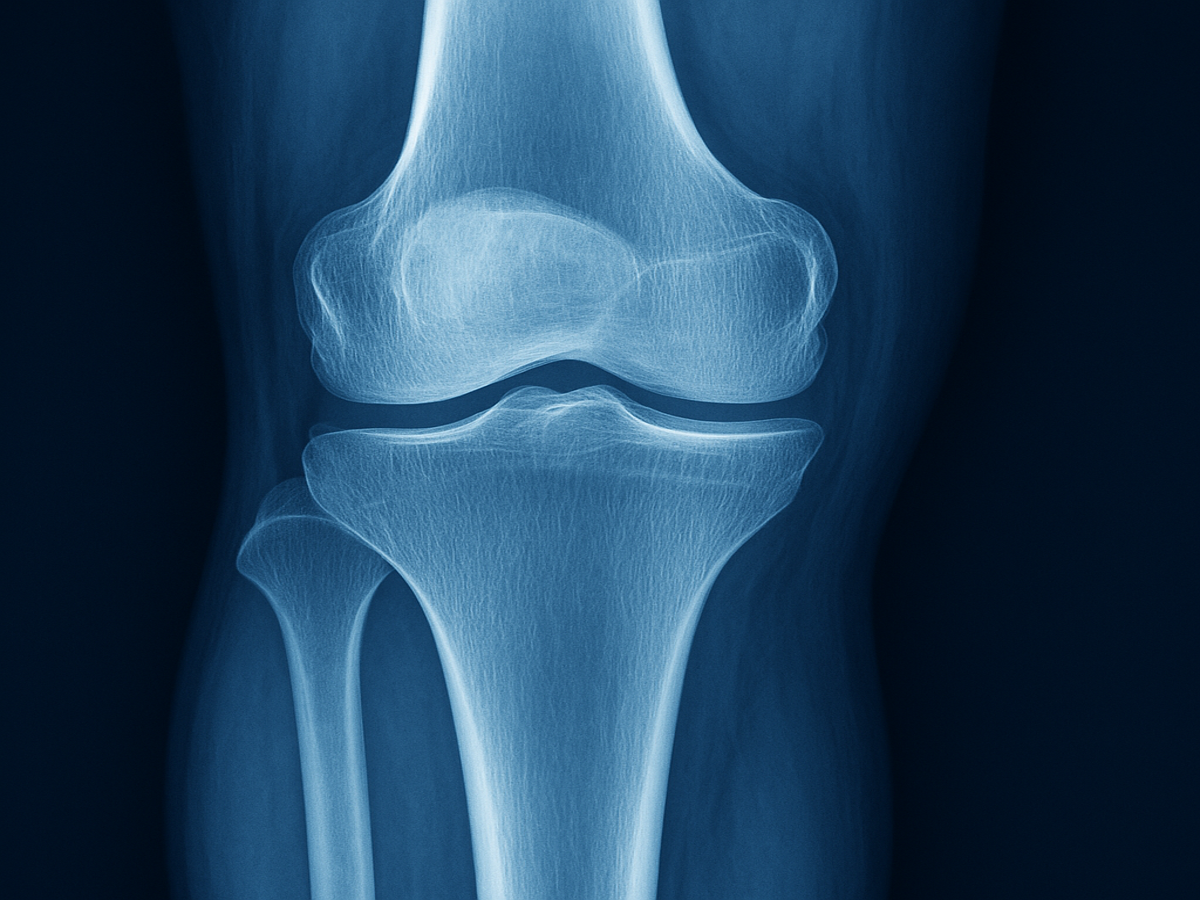

กระดูกอ่อนในข้อเข่าคือเนื้อเยื่อที่คลุมปลายกระดูกไว้ เพื่อช่วยลดแรงกระแทกระหว่างการเคลื่อนไหว เมื่อกระดูกอ่อนเริ่มสึกหรือบางลง กระดูกที่อยู่ใต้จะเสียดสีกันโดยตรง ทำให้เกิดอาการ “ข้อฝืด-ข้อดัง-ปวดเข่า” อย่างที่หลายคนคุ้นเคย

อาการปวดข้อเข่า เสียงก๊อบแก๊บ หรือข้อฝืดตึง เป็นสัญญาณเตือนของภาวะข้อเข่าเสื่อม ซึ่งเกิดจากการเสื่อมสลายของกระดูกอ่อนที่ทำหน้าที่รองรับแรงกระแทกในข้อต่อ เมื่อกระดูกอ่อนบางลงหรือถูกทำลาย กระดูกจะเสียดสีกันโดยตรง ทำให้เกิดอาการปวด บวม และเคลื่อนไหวลำบาก